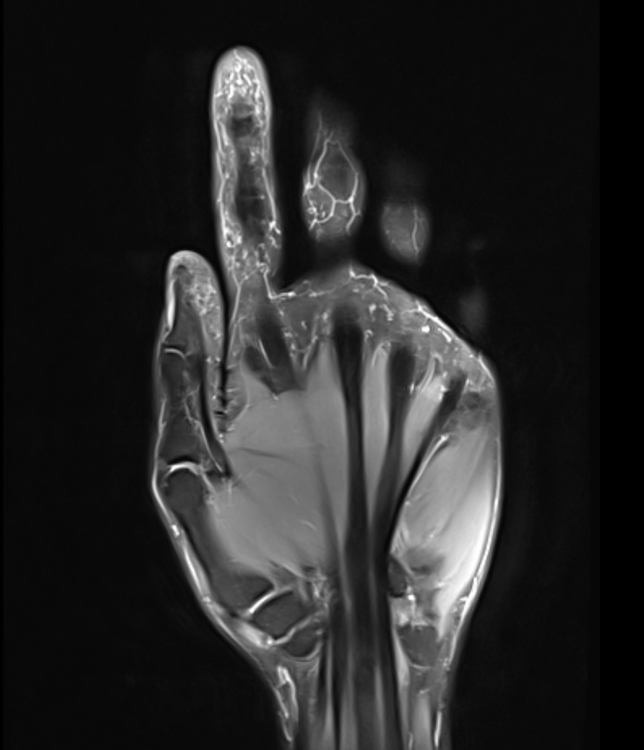

Ich wollte wieder ein Update geben. Und zwar war ich heute Morgen beim Radiologen und habe mir ein privat bezahltes MRT der rechten Hand machen lassen.

Die gute Nachricht ist, dass die Gelenke mit Ausnahme der Endgelenke soweit alle gut aussehen und es keine Wassereinlagerungen usw. gäbe. Was etwas verwunderlich war, ist die Tatsache, dass ich wohl Recht viele Kapilargefäße hätte. Am Zeigefinger ganz deutlich zu sehen, an den anderen Fingern auch vermehrt feststellbar. Dass es am Zeigefinger aufgrund der Psoriasis ist, sei möglich. Die anderen Finger sind ja bei der rechten Hand aber soweit unauffällig, nur dass hier und da vereinzelt die Gelenke zwicken.

Vielleicht ist das in den Gelenken auch eine Überlastung durch die Computerarbeit und vielen Handytippen und erklärt deshalb die Beschwerden.

Trotzdem interessant, wieso die Durchblutung da stärker sei, obwohl meine Finger ja meistens kalt sind 😂

Hier noch die MRT Bilder als Auszug für den interessierten Leser: